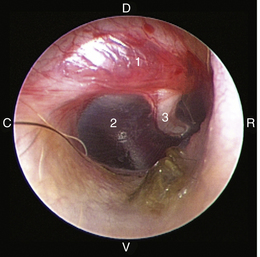

The middle ear consists of an air-filled tympanic cavity, three auditory ossicles, and the tympanic membrane. The tympanic membrane is located at a 45-degree angle in relation to the central axis of the horizontal part of the external ear canal. The tympanic membrane is a semitransparent membrane that separates the external ear canal from the middle ear, is thin in the center and thicker at the periphery, and is divided into two sections, the small upper pars flaccida and the larger lower pars tensa (Figure 20-2). The pars flaccida is the pink, small, loosely attached region forming the upper quadrant of the tympanic membrane that contains small blood vessels. The pars flaccida is usually flat; however, even in the healthy ear one may identify a bulging pars flaccida (Figure 20-3). The exception is the Cavalier King Charles Spaniel, in which a bulging pars flaccida may be indicative of a disease known as primary secretory otitis media (PSOM) (Figure 20-4).

image

Figure 20-2 Normal anatomy of the canine tympanic membrane of the right ear. 1, Pars flaccida; 2, pars tensa; 3, stria mallearis; C, caudal; D, dorsal; R, rostral; V, ventral.

(Courtesy of Dr. Lynette Cole, The Ohio State University, Columbus, Ohio.)

Figure 20-8 Normal canine tympanic membrane of the left ear. 1, Pars flaccida; 2, pars tensa; 3, stria mallearis; 4, bulla septum; C, caudal; D, dorsal; R, rostral; V, ventral.